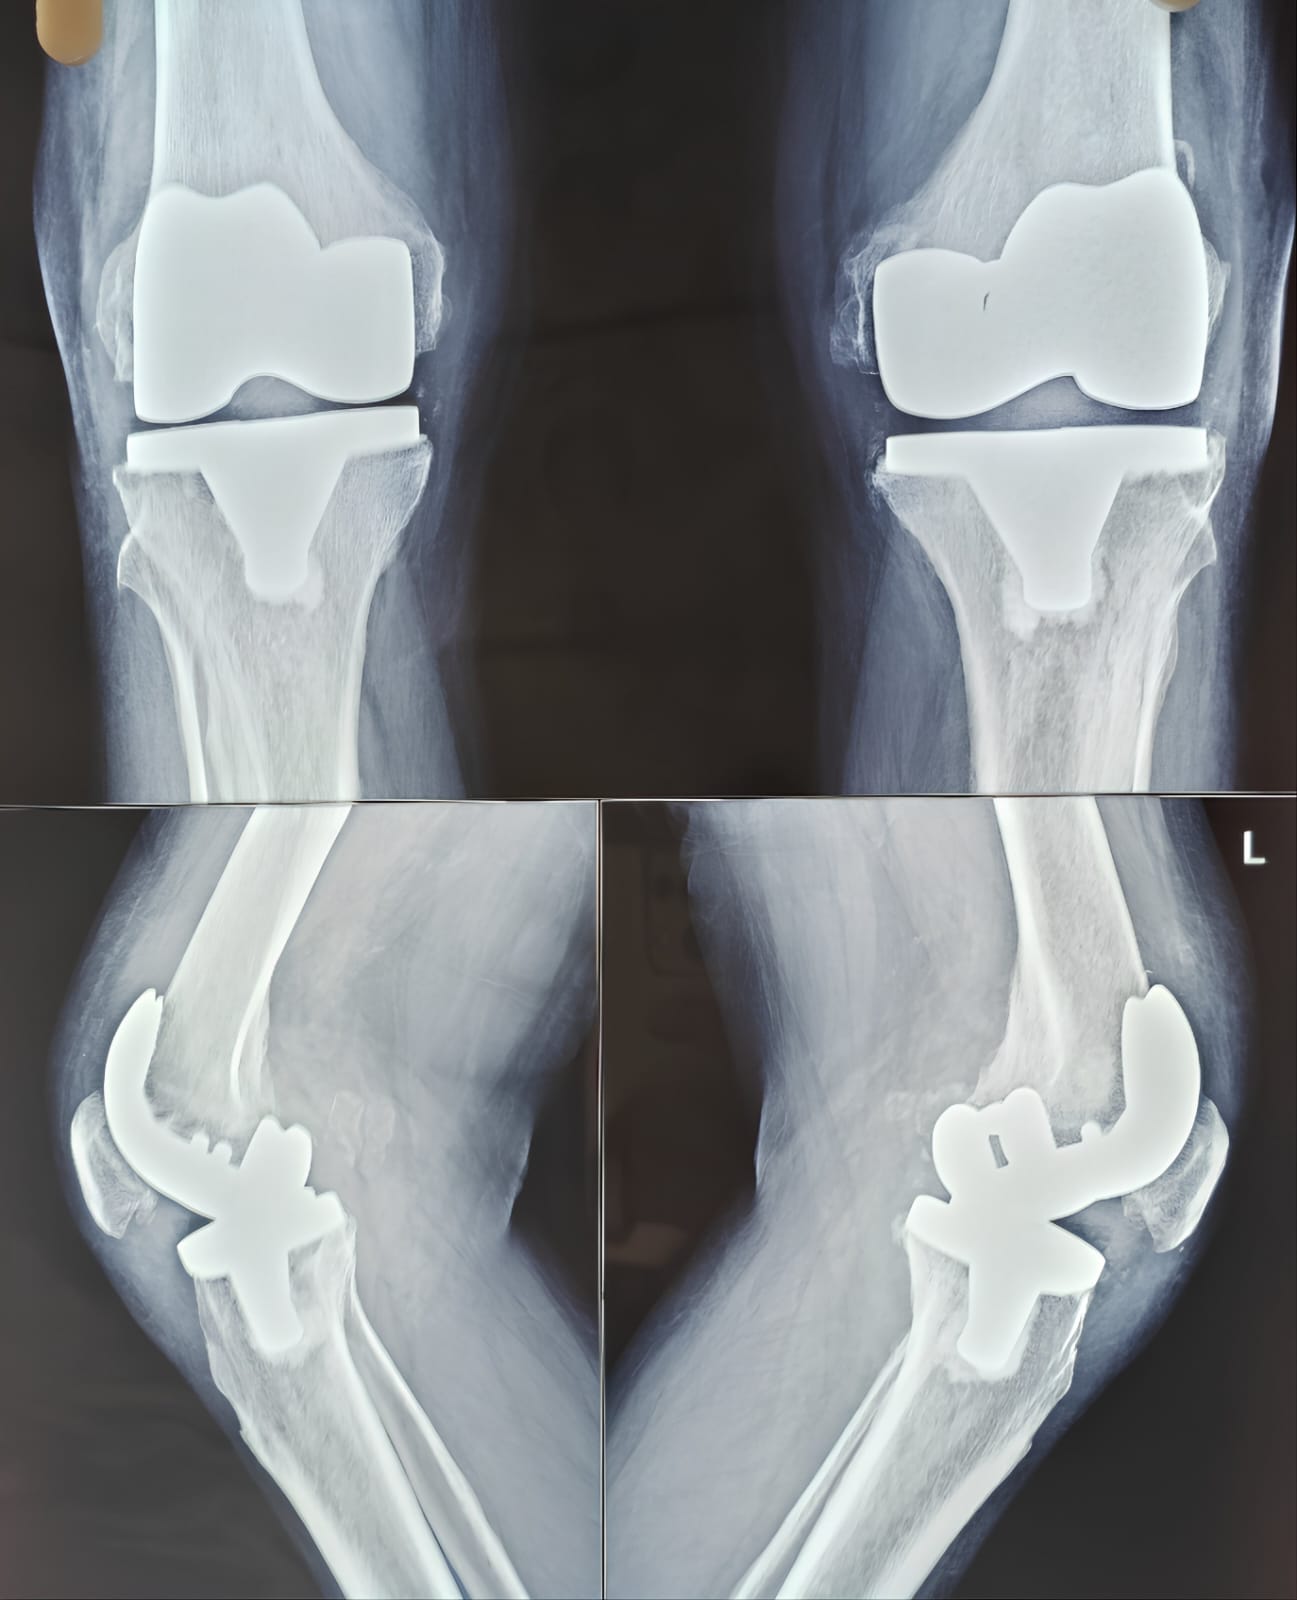

Total Knee Replacement